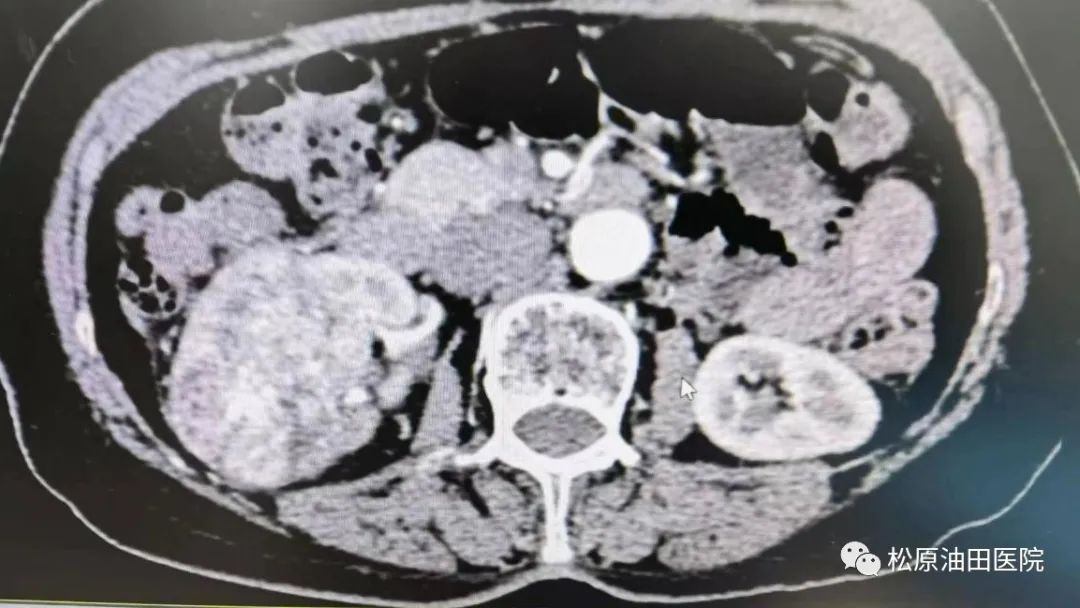

泌尿外科刘树志主任团队对吴大娘进行了详细的术前检查评估,结合术前增强CT结果,即肿瘤及血管与周围脏器粘连紧密的实际,为保证手术安全进行,防止术中出血过多进行术前备血;经科室讨论,手术方式选择腹腔镜下根治性肾切除术;泌尿外科联系麻醉科积极会诊,麻醉科选派经验丰富的李宜聪对患者进行全麻;刘树志主任术中仔细操作,克服肿瘤供应血管丰富、肾周与腹膜粘连紧密带来的手术难度与风险,历经2个小时时间,把右肾巨大肿瘤成功切除。目前患者术后恢复良好。